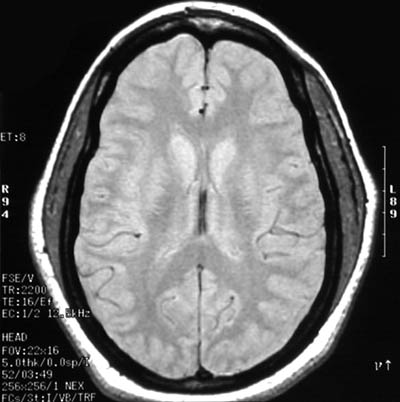

| In the axial FSE proton MRI scan of the head above can be seen marked temporalis muscle hypertrophy, particularly on the left. A coronal T2 weighted view is seen below. The temporalis muscle acts to close the jaw, bringing the mandible upward to the maxilla. Temporomandibular joint problems with difficulty chewing could produce such hypertrophy. Bruxism, which is gnashing, grinding, or clenching one's teeth, perhaps as a result of relatives who came to visit and stayed too long, could produce a similar result. |